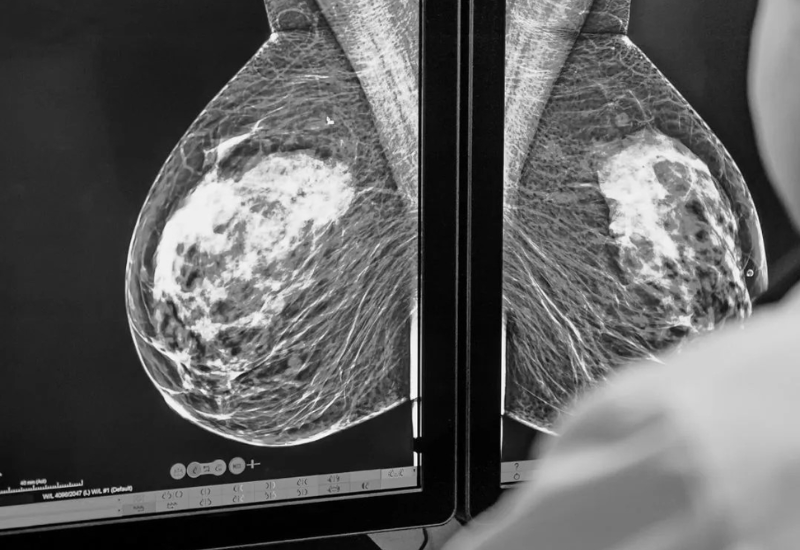

Chụp nhũ ảnh là một kỹ thuật chẩn đoán hình ảnh sử dụng tia X để ghi lại những hình ảnh chi tiết của tuyến vú. Kỹ thuật này cho phép nhận diện sớm các tổn thương, khối u và dấu hiệu vi vôi hóa mà khám thông thường khó phát hiện. Chụp nhũ ảnh được xem như một dạng X-quang chuyên biệt cho tuyến vú, đóng vai trò quan trọng trong sàng lọc và chẩn đoán ung thư vú.

Chụp nhũ ảnh giúp phát hiện sớm các tổn thương ở vùng vú

Trong quá trình thực hiện, tuyến vú được đặt trên tấm phẳng của máy chụp và nén nhẹ nhằm tạo hình ảnh chi tiết và rõ ràng hơn. Quy trình diễn ra nhanh chóng, ít gây khó chịu và an toàn, nhờ lượng tia X sử dụng rất nhỏ, không tác động đến cơ thể người bệnh.